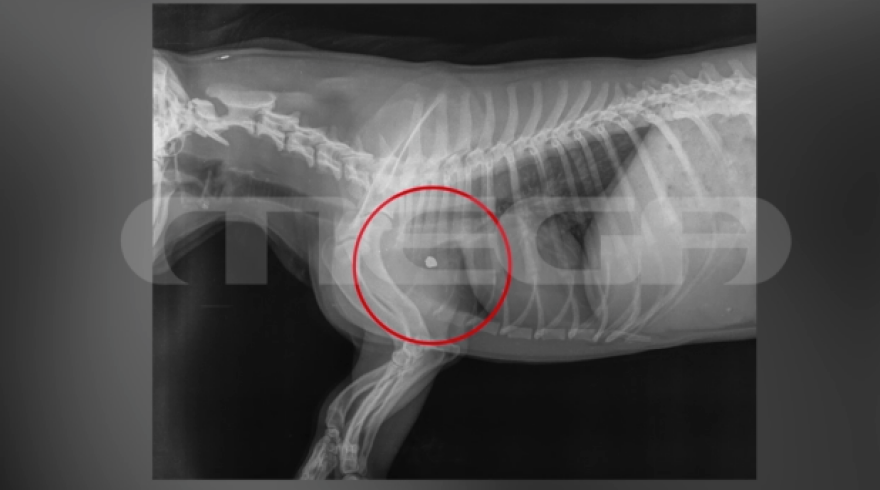

Η ακτινογραφία του σκύλου δείχνει τη σφαίρα καρφωμένη δίπλα από το μπροστινό του πόδι

Η ακτινογραφία του σκύλου δείχνει τη σφαίρα καρφωμένη δίπλα από το μπροστινό του πόδι.

«Η κτηνίατρος μας ενημέρωσε ότι το σκυλί δεν κινδυνεύει σοβαρά, είναι αγχωμένο, συγχυσμένο. Είναι δύσκολο να βγει η σφαίρα από το σώμα του ζώου, η σφαίρα είναι κάτι που χρειάζεται η αστυνομία για την έρευνα της».

«Ήξερε που πυροβολούσε, πυροβόλησε κοντά στην καρδιά. Η βολίδα αυτή τρύπησε το ζώο και για δύο εκατοστά δεν έφτασε κοντά στην καρδιά. Δεν μπορεί να γίνει χειρουργείο, η βολίδα έμεινε μέσα και ο σκύλος επιστράφηκε στην ιδιοκτήτρια», πρόσθεσε.